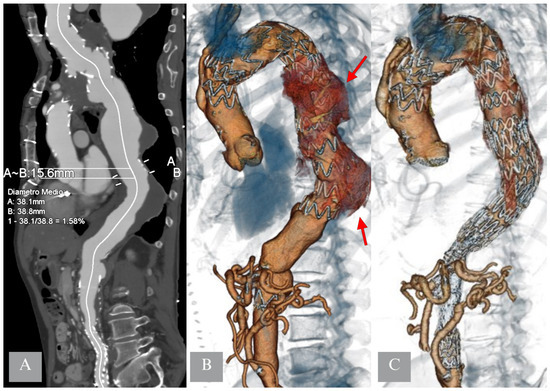

- Kasprzak, P.M.; Gallis, K.; Cucuruz, B.; Pfister, K.; Janotta, M.; Kopp, R. Editor’s choice—Temporary aneurysm sac perfusion as an adjunct for prevention of spinal cord ischemia after branched endovascular repair of thoracoabdominal aneurysms. Eur. J. Vasc. Endovasc. Surg. 2014, 48, 258–265. [Google Scholar] [CrossRef]

- Youssef, M.; Salem, O.; Dünschede, F.; Vahl, C.F.; Dorweiler, B. Adjunct Perfusion Branch for Reduction of Spinal Cord Ischemia in the Endovascular Repair of Thoracoabdominal Aortic Aneurysms. Thorac. Cardiovasc. Surg. 2018, 66, 233–239. [Google Scholar] [CrossRef]

- Jayia, P.; Constantinou, J.; Hamilton, H.; Ivancev, K. Temporary Perfusion Branches to Decrease Spinal Cord Ischemia in the Endovascular Treatment of Thoraco-Abdominal Aortic Aneurysms. AORTA 2015, 03, 56–60. [Google Scholar] [CrossRef]

- Harrison, S.C.; Agu, O.; Harris, P.L.; Ivancev, K. Elective sac perfusion to reduce the risk of neurologic events following endovascular repair of thoracoabdominal aneurysms. J. Vasc. Surg. 2012, 55, 1202–1205. [Google Scholar] [CrossRef] [PubMed]

- Mangialardi, N.; Lachat, M.; Esposito, A.; Puippe, G.; Orrico, M.; Alberti, V.; Fazzini, S.; Ronchey, S. The “Open Branch” Technique. Catheter. Cardiovasc. Interv. 2016, 87, 773–780. [Google Scholar] [CrossRef] [PubMed]